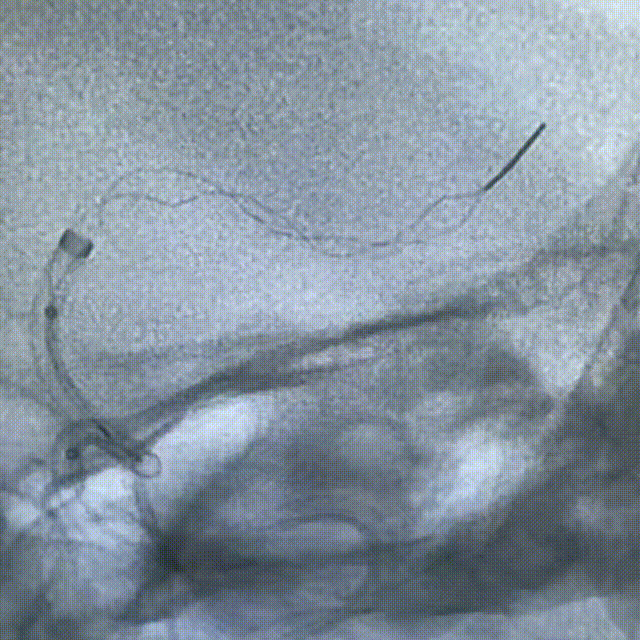

计划撤出内部器械前充盈近端BMAX088球囊长鞘,阻断前向血流,并持续抽吸提供负压。

取栓支架置于大脑中动脉水平段,中间导管在闭塞近端持续抽吸,在BMAX088球囊长鞘近端负压保护下,将支架及中间导管撤出。

动脉长鞘怎么置入健谈•一鞘双能|温昌明教授团队:BMAX088球囊长鞘治疗左侧大脑中动脉闭塞一例_https://www.jmylbn.com_新闻资讯_第9张

动脉长鞘怎么置入健谈•一鞘双能|温昌明教授团队:BMAX088球囊长鞘治疗左侧大脑中动脉闭塞一例_https://www.jmylbn.com_新闻资讯_第10张

动脉长鞘怎么置入健谈•一鞘双能|温昌明教授团队:BMAX088球囊长鞘治疗左侧大脑中动脉闭塞一例_https://www.jmylbn.com_新闻资讯_第11张